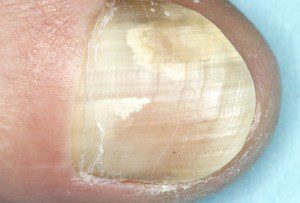

عفونت قارچی ناخن

باعث ضخیم شدن ناخن ، تغییر رنگ و شکننده شدن ناخن میشود واز فردی به فرد دیگر قابل انتقال بوده است ، در موارد خفیف کرم های موضعی می تواند به فرد کمک کند اما در موارد شدید تر ، استفاده از داروهای ضد قارچ می باشد.